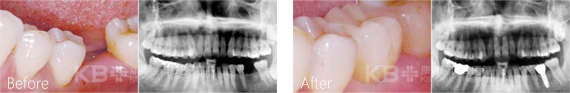

康贝佳经典种植案例

第三次赵大爷下定决心要去种牙,提前预约到了意大利种植牙博士法布里奇奥。针对赵大爷的情况,法布博士给他选择了即刻种植牙技术配合“缺多种少”ALL-ON 4方案,仅需4颗植体恢复半口牙,而且几乎没有疼痛和不适,还省下了不少费用,让赵大爷开心不已。>>>查看赵大爷的种牙费用

赵大爷采用的All-on-4种植牙技术

All-on-4技术对医生的技术和设备有着较高的要求,不是每家医院都可以开展,康贝佳口腔数字化先进设备,针对国人口型对“All-on-4”进行升级和改造,准确种植,安全施术!

All—on—4半口牙缺失更好的种植技术

All—on—4种植技术是欧美先进的口腔种植技术,主要针对于全口无牙或者半口无牙的情况下,利用4颗种植体,于两颗前牙部位的种植体垂直植入牙槽骨内,而两颗中远部位的种植体采取倾斜角度植入牙槽骨内,然后在种植体的基台上安装“拱形连桥”牙冠,这样整个种植牙的受力就呈现出“拱形”的特征,完成口腔种植修复。